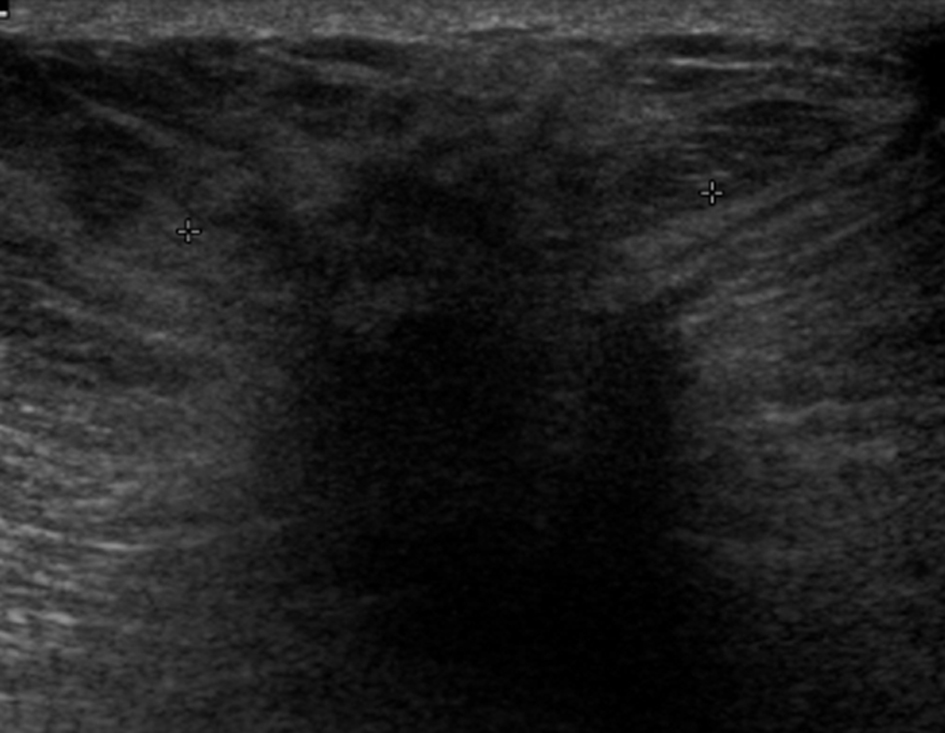

A galactocele (Fig. 1) is the most common benign mass lesion diagnosed during lactation. It often develops following cessation of breastfeeding, when milk is stagnant [1]. This can lead to duct dilatation and obstruction/rupture, with extravasation of milk into the surrounding stroma. Galactoceles can be associated with inflammation and necrosis [1]. Clinically a galactocele appears as a well circumscribed smooth mass that is often mobile [5].

![]() Click for large image | Figure 1. Complex cystic mass on ultrasound. Fine needle aspiration confirmed a galactocele. |

Ultrasound findings are those of a simple or complicated cyst, with a well circumscribed, ovoid, anechoic or hypoechoic mass showing posterior acoustic enhancement [6]. The appearance on ultrasound and mammography can be variable depending on the fat and protein content present [1]. Aspiration of a galactocele is both diagnostic and therapeutic.